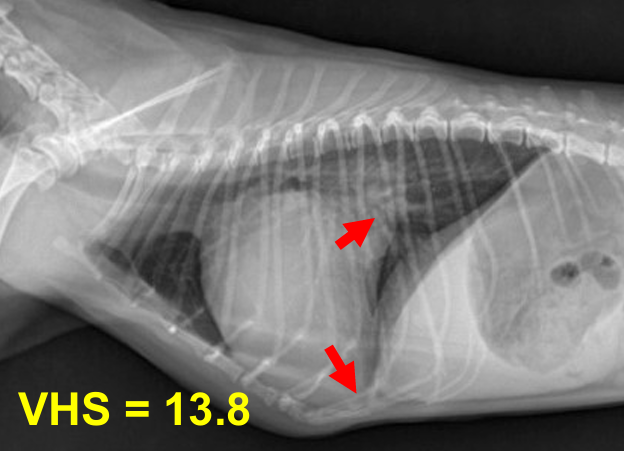

1기 (Moderate : 좌심방귀 볼록한 정도)

1) 심장 커짐

Cardiomegaly, left auricle 확장, 전허리/후허리 소실 : 심장이 부풀면서 일자형이 됨.

+ Sternal contact : 심장과 sternum 거리 좁아짐